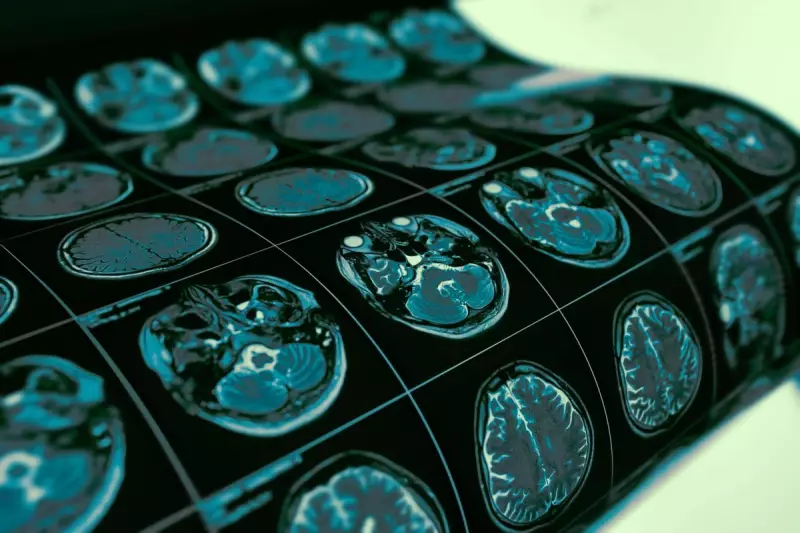

The decision by NICE (National Institute for Health and Care Excellence) means thousands of patients with specific low-grade gliomas will be denied access to vorasidenib, a drug hailed as the first major breakthrough in brain cancer treatment in decades.

Vorasidenib represents a monumental advancement in neuro-oncology, specifically targeting IDH-mutant diffuse gliomas. Clinical trials demonstrated remarkable results, with the drug reducing the risk of disease progression or death by an impressive 61%.